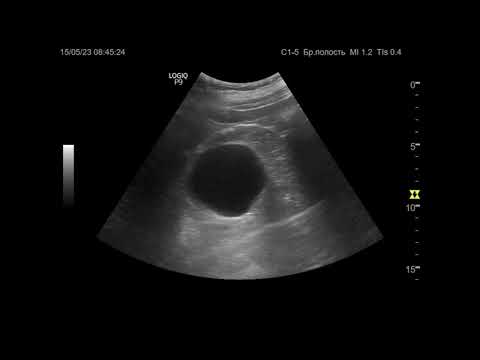

Ультразвуковая диагностика (УЗИ). Доктор Иогансен. Видеопримеры. Выпуск 17. Кисты почек.

Ультразвуковая диагностика желчекаменной болезни.